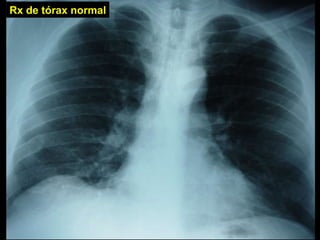

Rx de tórax normal

Evaluación clínica ante sospecha de TEP Historia   Factores de riesgo Exploración física Pruebas sencillas no son específicas para TEP: Rx tórax Gasometría arterial Electrocardiograma Probabilidad clínica de TEP: implícita o explícita